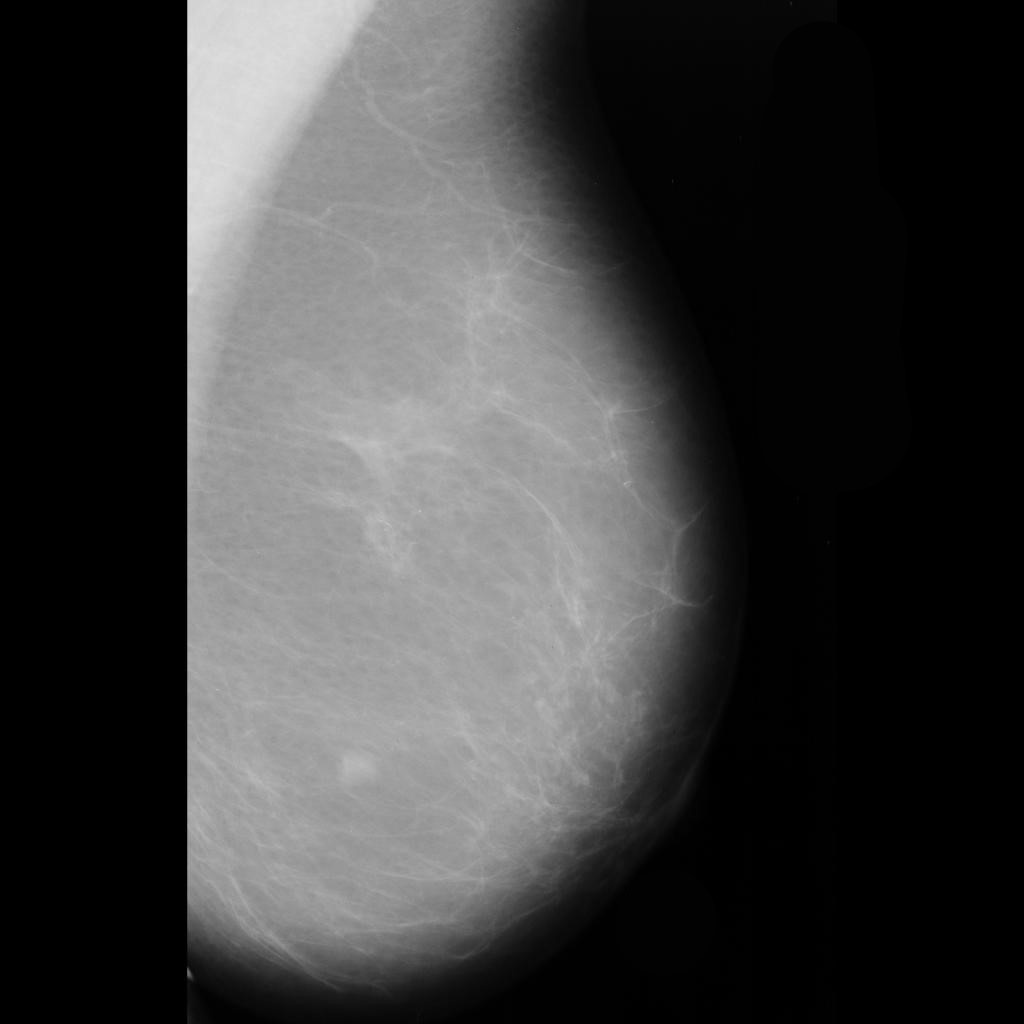

malignant